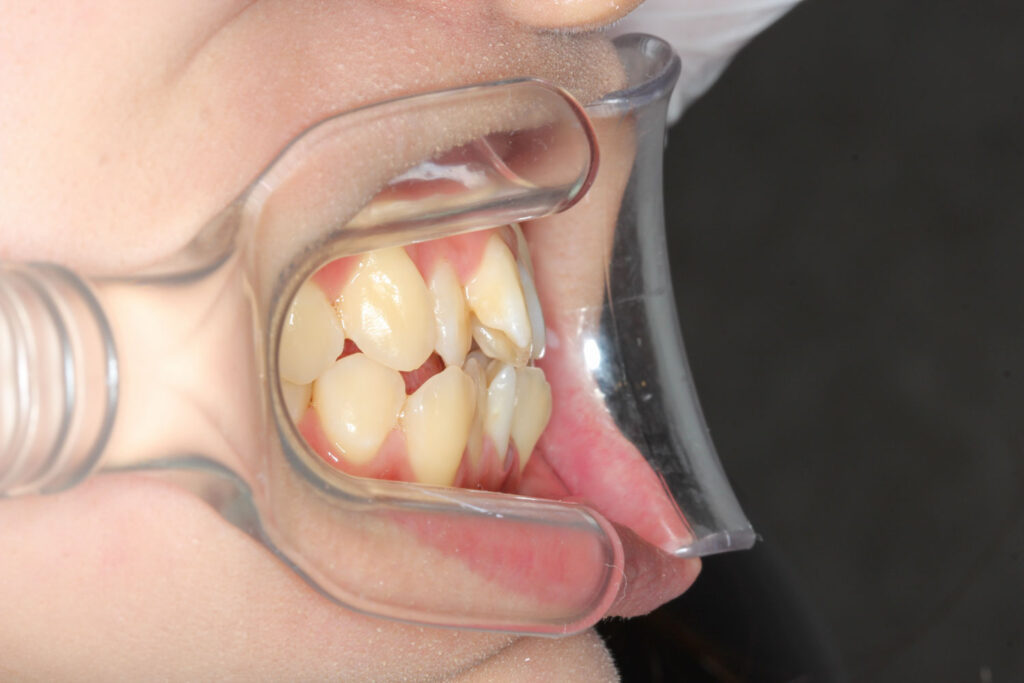

Before

After

年齢 10代

治療装置 上は裏側の矯正装置(フルリンガル)

治療内容 非抜歯

治療期間 2年8か月

リスク 歯の移動に伴う痛み、歯肉退縮、歯根吸収、歯肉炎、虫歯

主訴 ガタガタと隙間が気になる

症状 叢生と正中離開

治療回数 36回程度

総額費用 140万円程度